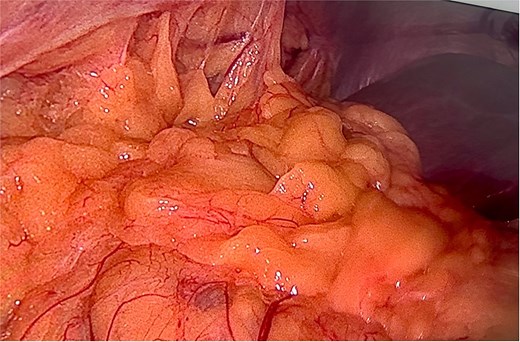

A right diaphragmatic hernia secondary to blunt abdominal trauma was diagnosed. The patient underwent laparoscopic right diaphragmatic hernia repair with mesh hernioplasty. Intraoperatively, a large defect in the right hemidiaphragm allowed omentum and hepatic flexure herniation with dense adhesions (Fig. 3). Due to the chronicity and size of the defect, complete primary closure was not feasible (Fig. 4). The defect was subsequently reinforced with a 20 × 15 cm intraperitoneal composite mesh fixed with tackers to ensure robust repair (Fig. 5). The surgical intervention was successful. The patient was discharged on Day 3, and a 5-month follow-up CT confirmed correct mesh positioning without complications (Fig. 6).

After releasing, the herniated components and reducing them back into the abdominal cavity.